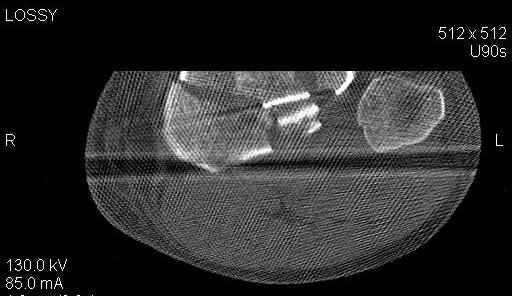

Пациенту сделали КТ - ухитрились сделать на шине Белера (не давал положить прямую ногу) - срезали передний отдел. Планируется на пятницу (24.12) на операцию - синтез длинной мыщелковой LCP-пластиной Synthes :). Отек ближе к слову умеренный (окружность голени +4 см по сравнению со здоровой). КТ и снимок на вытяжении прилагаются.

На представленных предоперационных срезах КТ огромный задне-медиальный фрагмент расположен больше кзади, чем медиально. Для планирования, кроме поперечных срезов, надо ориентироваться на корональные срезы, которые укажут топографию верхушки медиального фрагмента.